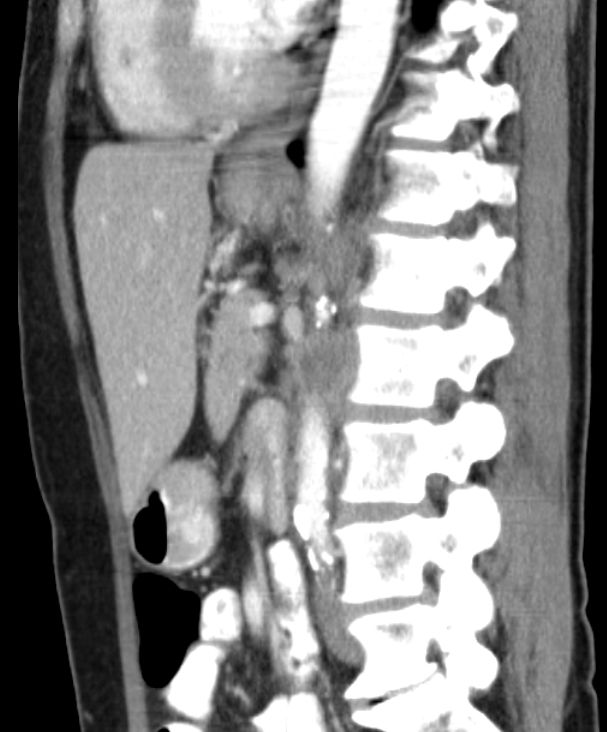

| paraaortale Lymphknoten - Metastasen | 54-jährige Frau, die vor 4 Jahren wegen eines

Zervix - Karzinoms FIGO IIIb mit Radiochemotherapie behandelt wurde. Damals praevesikaler Harnstau beiderseits. Jetzt neu Harnstau links. RF links paraaortal. ![]() | |||

![]() |

![]() | |||